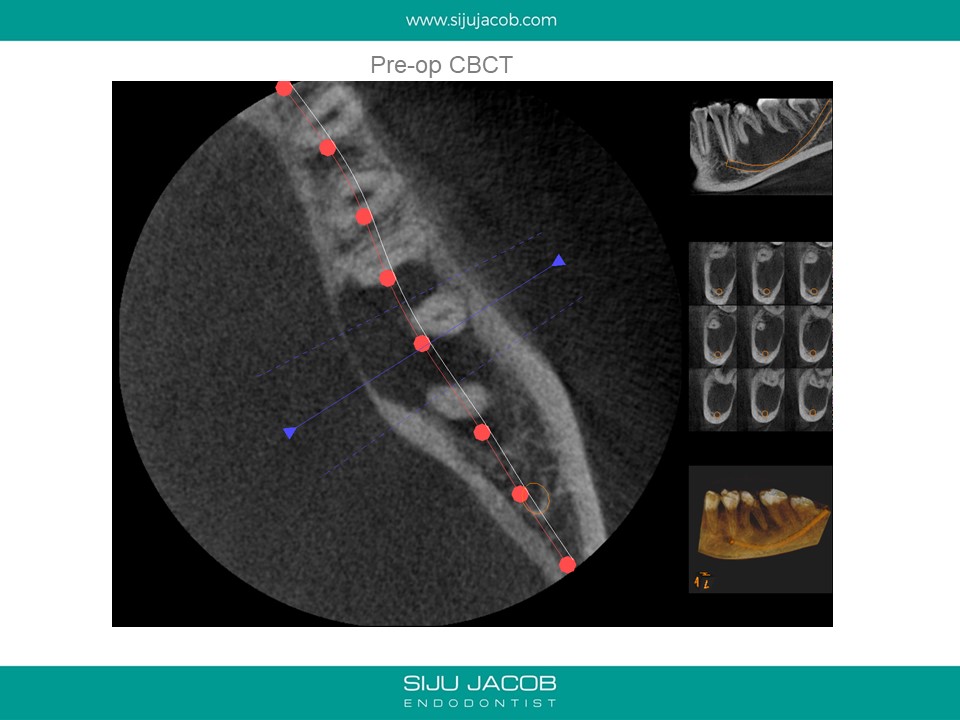

This was a 15 year old girl with a large peri-apical lesion in relation to the the left mandibular first molar. The tooth had a guarded restorative prognosis. The goal of endo in this case was to hold the tooth for a longer period before placing implants and also get some bone to fill in which would make implant placement more viable. I held the tooth with calcium hydroxide dressing for 5 months, saw some bone-fill and obturated the tooth. A crown was also placed. 3-year recall shows the tooth still going strong.